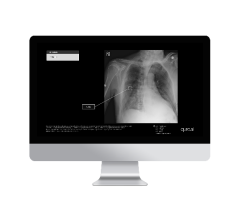

Dec. 12, 2024 — Lunit, a provider of AI-powered solutions for cancer diagnostics and therapeutics, recently announced ...